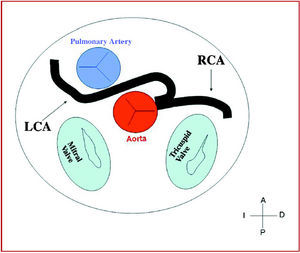

3. Preaortic or interarterial (between the aorta and the pulmonary artery), in which the anomalous right coronary, left anterior descending or left main coronary artery cross the septum or the aortopulmonary space. This is the course that has most frequently been related to signs of ischemia and/or sudden death (Figures 7 and 8).

Figure 8. Diagram showing the interarterial course of a left coronary artery (LCA) originating in controlateral sinus.